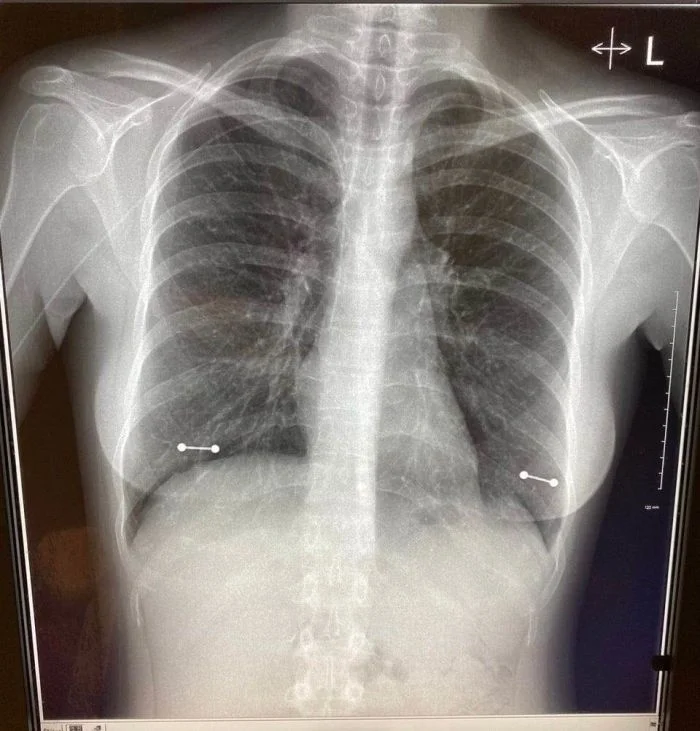

Девушка забыла снять пирсинг во время прохождения рентгена

Украшения и пирсинг можно не снимать во время рентгеновского обследования, если у вас они сделаны из качественного имплантационного титана.